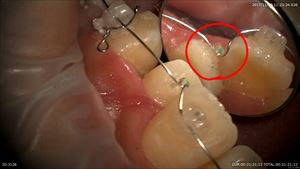

重症度判定は済んでいますので適切な量の麻酔をマイクロスコープ下で行いラバーダム。他院で行われた仮蓋を外すと

多量の感染源が。。感染が取り切れていない。汗

上部形成とストレートラインアクセス

丁寧に感染源をとります。無痛で患者さまに喜んで頂けています。